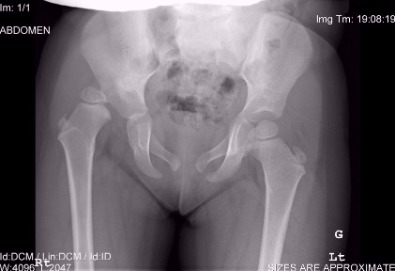

Πέντε χρονών κορίτσι με εγεφαλική παράλυση πριν από χειρουργική επέμβαση. Οι ακτινογραφίες έδειξαν υπεξάρθρημα ισχίου.

Μετεγχειρητικό βίντεο πιο πάνω ασθενούς σε διάστημα ενός χρόνου μετά τη χειρουργική επέμβαση. Το αριστερό ισχίο έχει ανακαταχθεί.

Συγγενές εξάρθρημα του ισχίου

Προεγχειρητικές ακτινογραφίες κοριτσιού ηλικίας τρεισήμιση ετών στην Κύπρο, που παρουσιάστηκε με χολώτητα λόγω συγγενούς εξάρθρωσης του δεξιού ισχίου

Οι πιο πρόσφατες μετεγχειρητικές ακτινογραφίες (4 χρόνια αργότερα) μετά από ανοικτη ανάταξη και οστεοτομίες μηριαίου και λεκάνης. Η ασθενής έχει φυσιολογικό βάδισμα